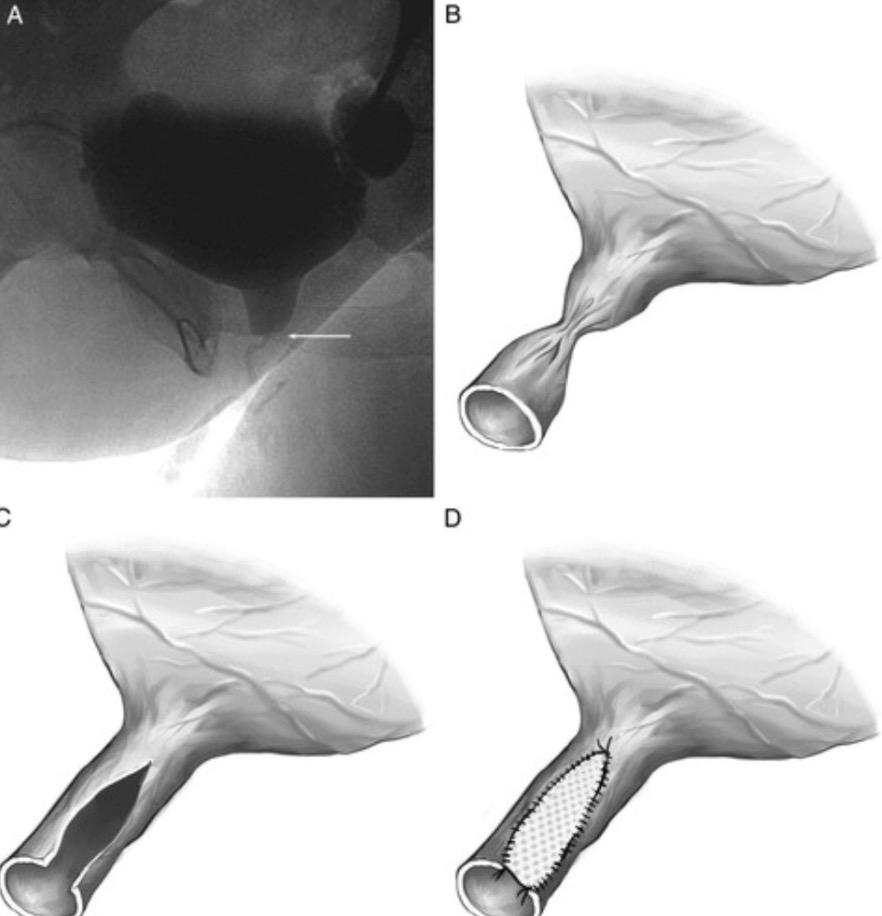

Açık ameliyatlarda (üretroplasti) uç uca birleştirme mi yoksa yamalarla genişletme mi?

Uçuca birleştirme özellikle dar üretra segmentinin kısa olduğu hastalarda öncelikle tercih edilebilir. Fakat burada dikkat edilmesi gereken en önemli husus, uçuca getirilecek olan segmenti canlı ve sağlıklı üretra dokusu olmasıdır. Aksi takdirde iyi kanlanmayan, atrofik bir üretranın birleştirilmesi sonrası darlık tekrar edecektir. Bu durumda sağlıklı üretra doksuna kadar hastalıklı kısım çıkarılmalıdır. Bu işlemden sonra darlık segmenti 2 cm den uzun olacaksa, otolog (hastanın kendi dokusundan) yamalar kullanılmalıdır.

Yama olarak ağız içi, dil altı ve cilt yamaları tercih edilmektedir. Fakat özellikle ağız içi mukoza diğer yamalara göre daha başarılı sonuçlar vermektedir. Bunun nedeni üretral mukozanın ıslak bir mukoza olması ve bunu en iyi taklit eden dokunun ağız içi mukozası olmasıdır. Ağız mukozası alındıktan sonra dikkatlice inceltilmelidir. Bu sayede destek aldığı, temas ettiği dokulardan yeterli kanlanma gerçekleşebilmektedir. Ayrıca ciltten alınan flap (damarlı doku) veya greftler sonrası kıllanma sorunuyla karşılaşılabilmektedir. Bunun yanında dokuların transfer sonrası büzüşerek küçülmesi ağız mukozasında diğer yamalara göre daha az oranda olmaktadır.

Kadın üretra darlıklarında iki tür yaklaşım benimsenir. Yama veya flap (damarsal köklü doku) ile onarım. Yama olarak yine ağız mukozasını ideal yama olarak kullanmaktayız. Flap olarak ise özellikle vajenden farklı tekniklerle oluşturulan flapler üretranın yerini alarak darlığın tamirinde etkili rol oynamaktadır.

Bu ameliyatta uretra darlığın olduğu bölgeye kadar saat 12 hizasından açılır. Darlık bölgesini genişletecek yamalar sıkı bir şekilde sabitlenir. Sonrasında vajinal doku ile yama ve uretral kalan kısım anastomoz edilir (birleştirilir). Erkeklerdeki üretroplasti ameliyatlarındaki gibi bu hastalarda da sonda 3 hafta süreyle tutulur.